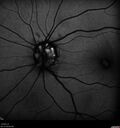

Macular fold - resolved with time69 viewsApr 14, 2025